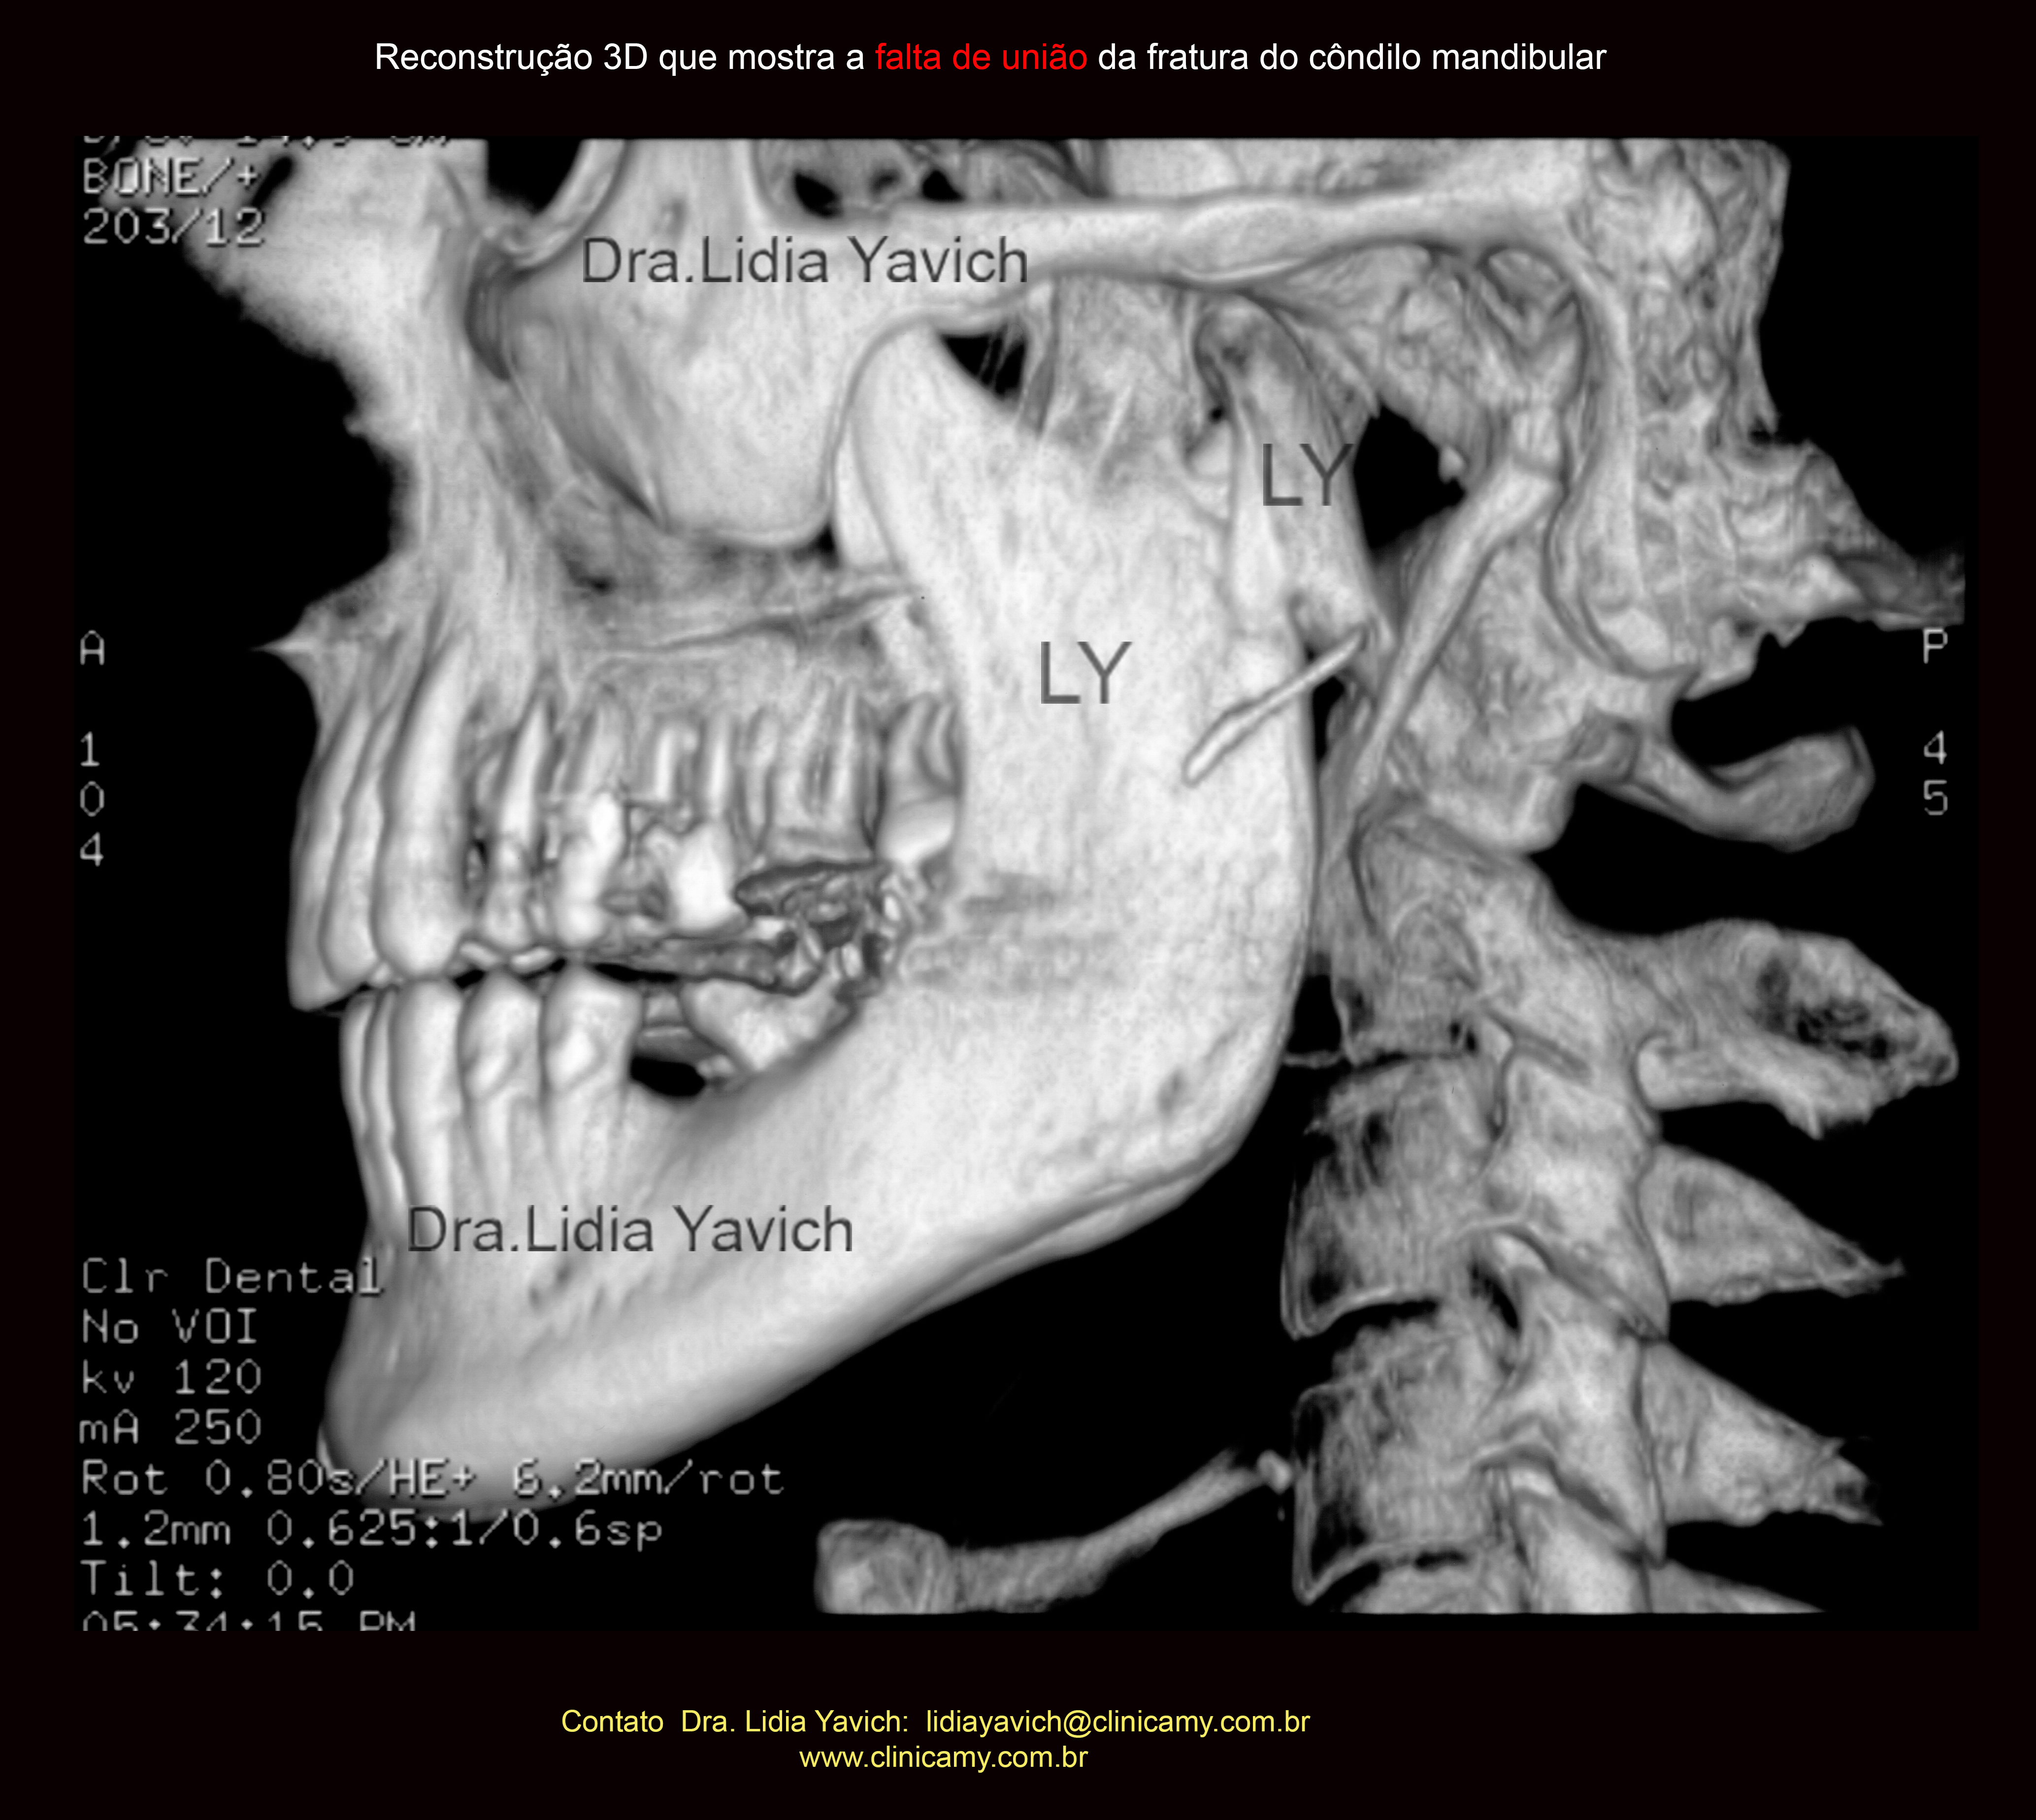

Reconstrução em 3D mostrando a falta de união total da fratura do côndilo mandibular, quatro meses após a cirurgia.

Outra reconstrução em 3D mostrando a falta de união total da fratura do côndilo mandibular, quatro meses após a cirurgia.

Reconstrução em 3D mostrando a falta de união do côndilo mandibular esquerdo após quatro meses da cirurgia e a posterior união do côndilo mandibular após o tratamento neurofisiológico.